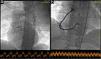

Figure 4.

Thrombotic material retrieved via aspiration thrombectomies.

The coronary angiogram showed simultaneous acute thrombosis of the right coronary artery (RCA) (Figure 2a) and of the left anterior descending (LAD) artery (Figure 3a). Initially, to visualize suspected plaque rupture and to aid the decision whether to implant stents, multiple aspiration thrombectomies were performed, resulting in removal of substantial amounts of thrombotic material (Figure 4). After intravenous and intracoronary administration of abciximab, an everolimus-eluting stent was implanted into the RCA, restoring good epicardial coronary flow (Figure 2b). In the LAD spontaneous reperfusion occurred, revealing a massive thrombus (Figure 3b). After aspiration thrombectomy, a stent was implanted (Figure 3c). Echocardiographic examination revealed inferior wall and basal septal akinesis with ejection fraction of 35%. Right ventricular enlargement (5.4 cm in apical 4-chamber view) and hypokinesis (tricuspid annular plane systolic excursion [TAPSE] 14 mm) were present. Right ventricular function was improved on control echocardiography (TAPSE 27 mm).